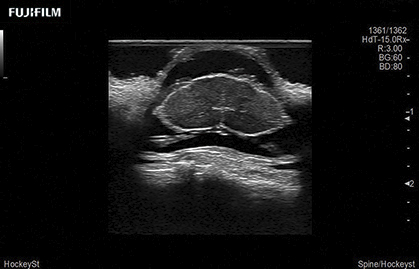

Spinal Procedure using L53K

Hockey-stick linear array transducer is the transducer of choice for spinal scanning, providing exceptional near and far-field resolution. Its low profile design lends itself perfectly to the spatial confines of spinal surgery.